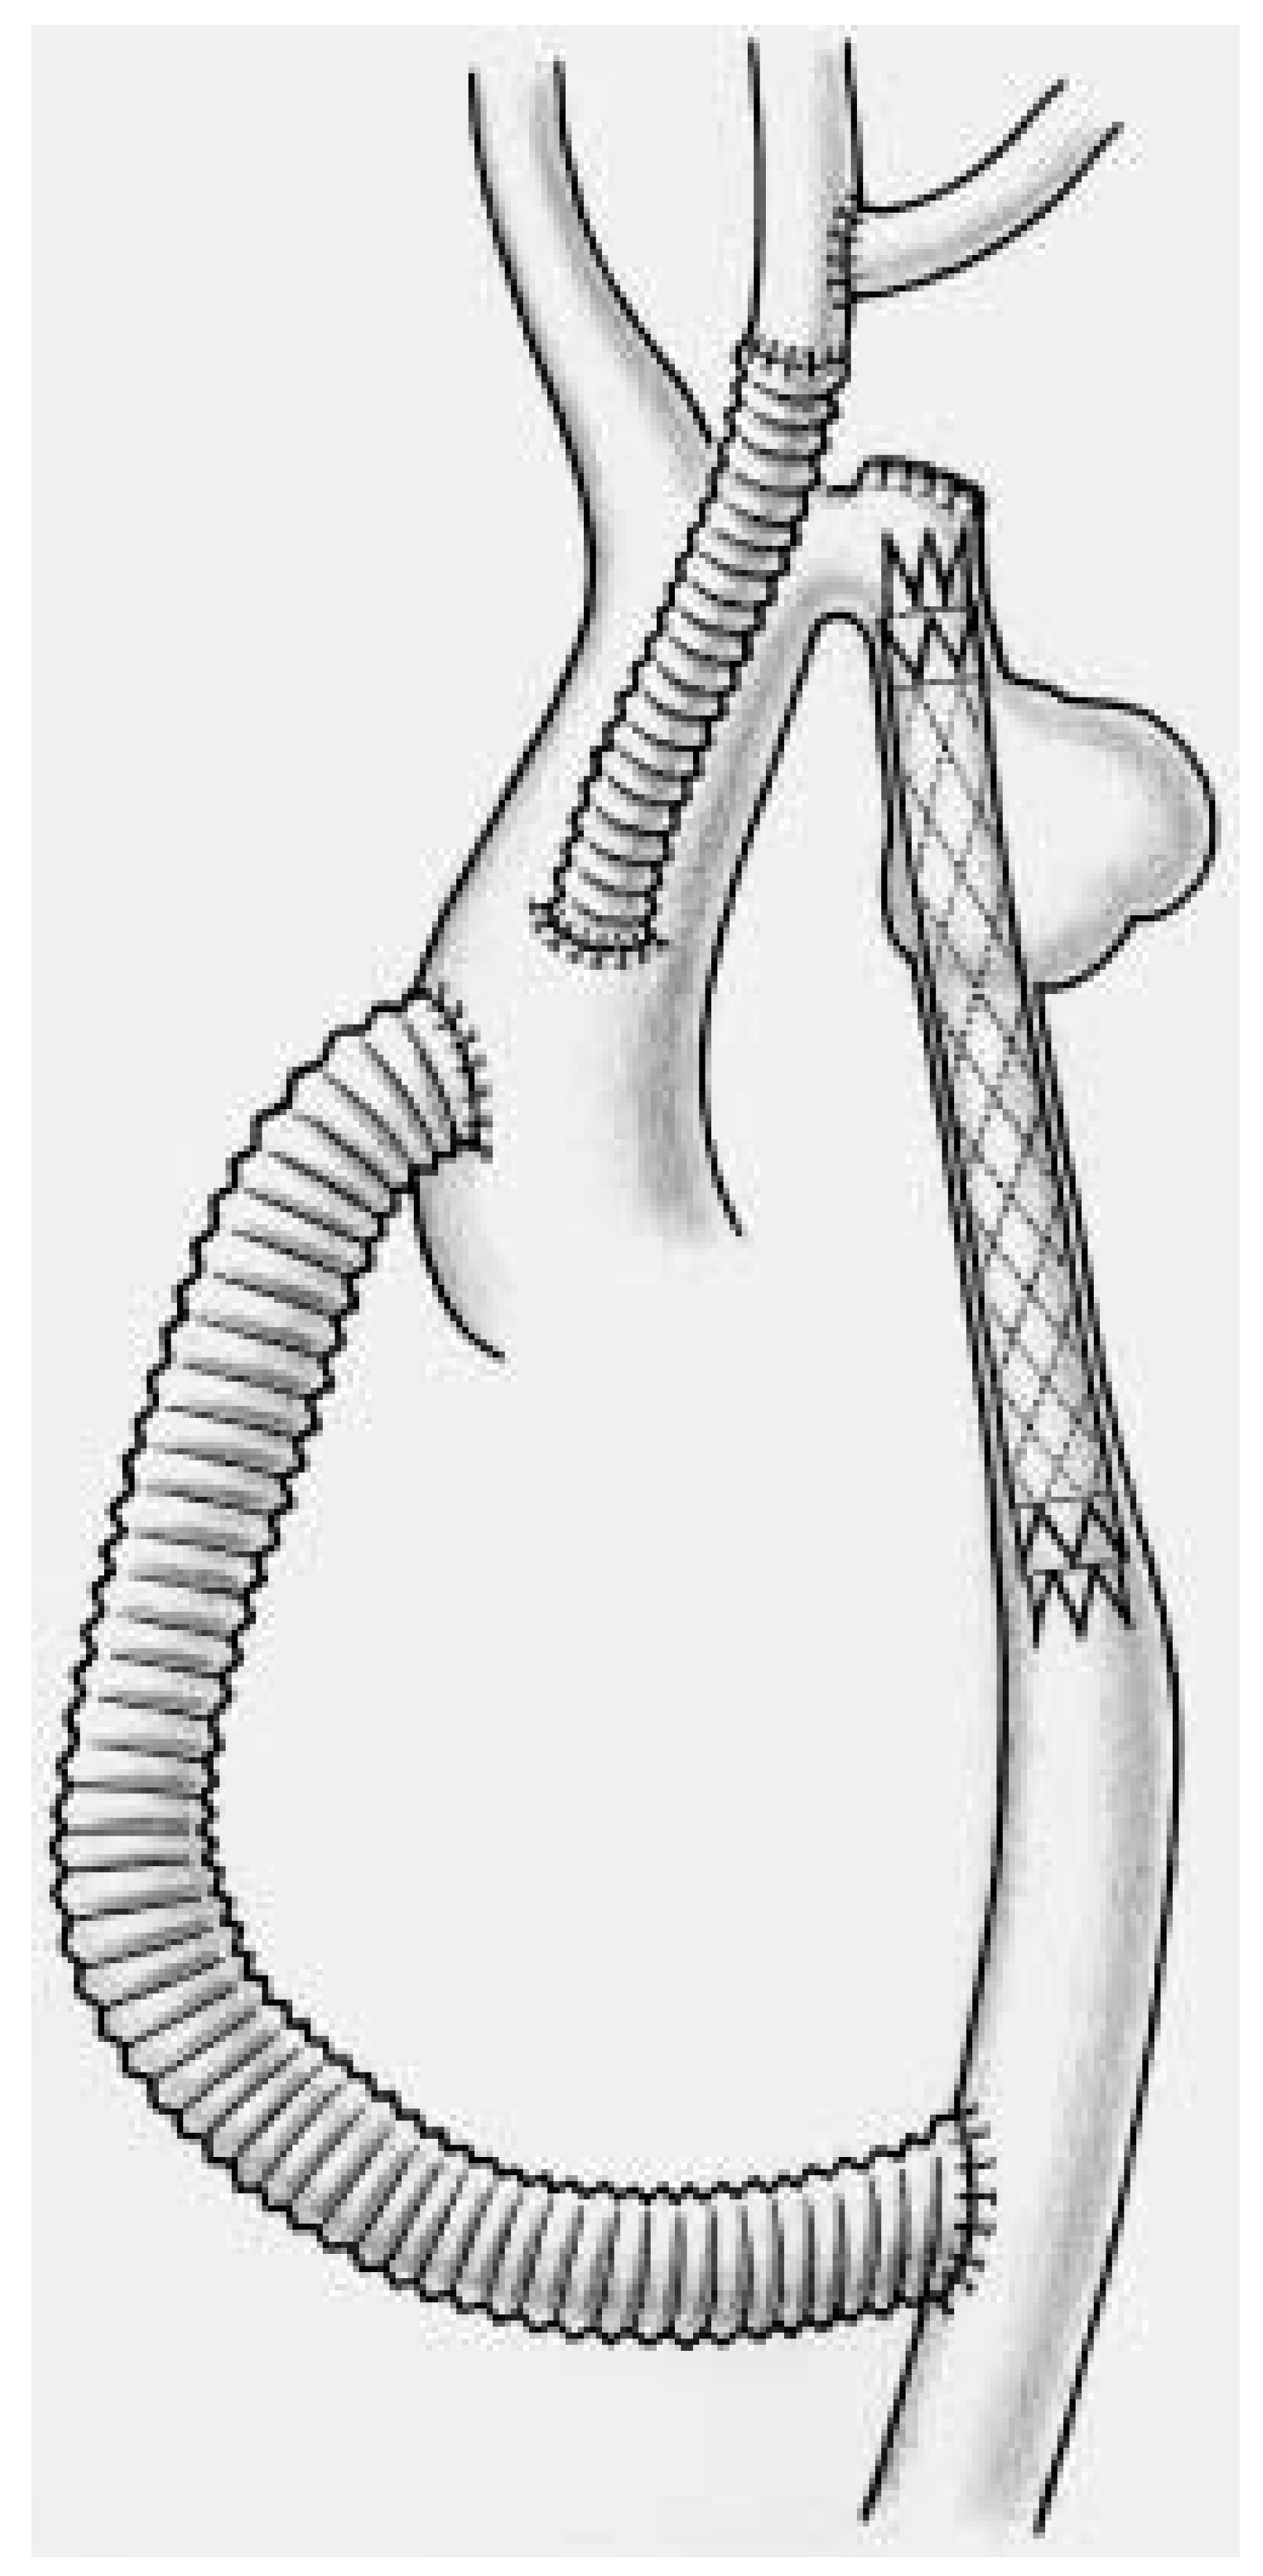

The left subclavian artery is either transposed into the left carotid artery or revascularised at the end of the procedure using an additional 8 mm graft (Figure 3 and Figure 4).

Figure 3.

Schematic representation of the combined surgical/endovascular approach which allows complete repair of the aortic arch following debranching and revascularization of the supraaortic vessels.

Finally, a covered Wall-Graft stent-graft prosthesis was inserted within the previous Wallstent, expanded into the mid aortic arch and the proximal descending aorta and allowed complete exclusion of the aneurysm (Figure 5).

Figure 5.

Artist drawing of the situation following Wallstent insertion to treat complex coarctation. The hypoplastic aortic arch remained untreated (!!).